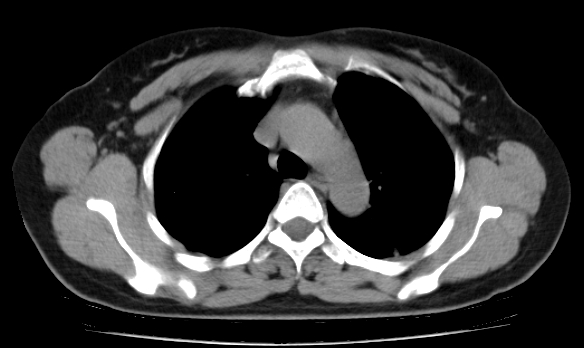

标题: CT25227:背部疼痛伴双侧胸壁痛2月,食欲差。 [打印本页]

标题: CT25227:背部疼痛伴双侧胸壁痛2月,食欲差。

肺结核并胸椎结核?请各位高手指教。

用椎体的条件来扫胸椎呀!考虑1左侧胸膜小结节形成2椎体结核并冷脓肿形成

考虑胸椎结核并椎旁软组织肿胀。

左肺结核灶,胸椎结核并冷脓肿。

左肺结核灶,胸椎结核并冷脓肿